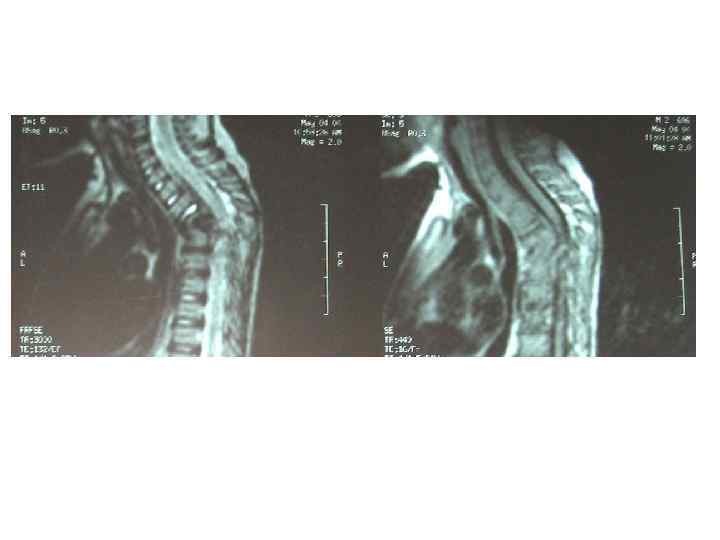

Последствия туберкулезного спондилита, перенесенного в детстве (МРТ)